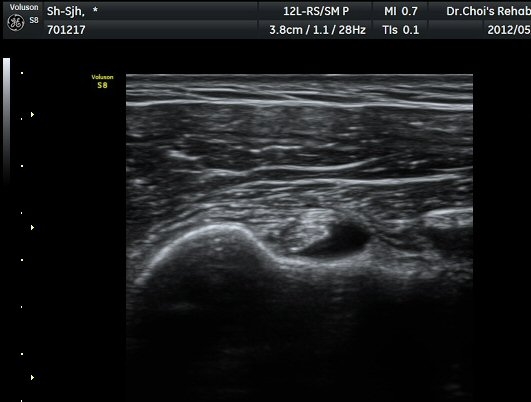

µÈ´Ù(»çÁø 3). ±Ø»ó°Ç Á¾´Ü¸é°Ë»ç»ó ±Ø»ó°Ç ºÎÂøºÎ¿¡ °í¿¡ÄÚ µ¢¾î¸®°¡ °üÂûµÇ°í(»çÁø 4, 5)

ÆÄ¿öµµÇ÷¯ °Ë»ç¿¡¼­ Ç÷·ùÁõ°¡¸¦ º¸ÀδÙ(»çÁø 6).  Ⱦ´Ü¸é°Ë»ç¿¡¼­µµ °í¿¡ÄÚ µ¢¾î¸®¿Í

Ç÷·ùÁõ°¡°¡ È®ÀεȴÙ(»çÁø 7, 8).